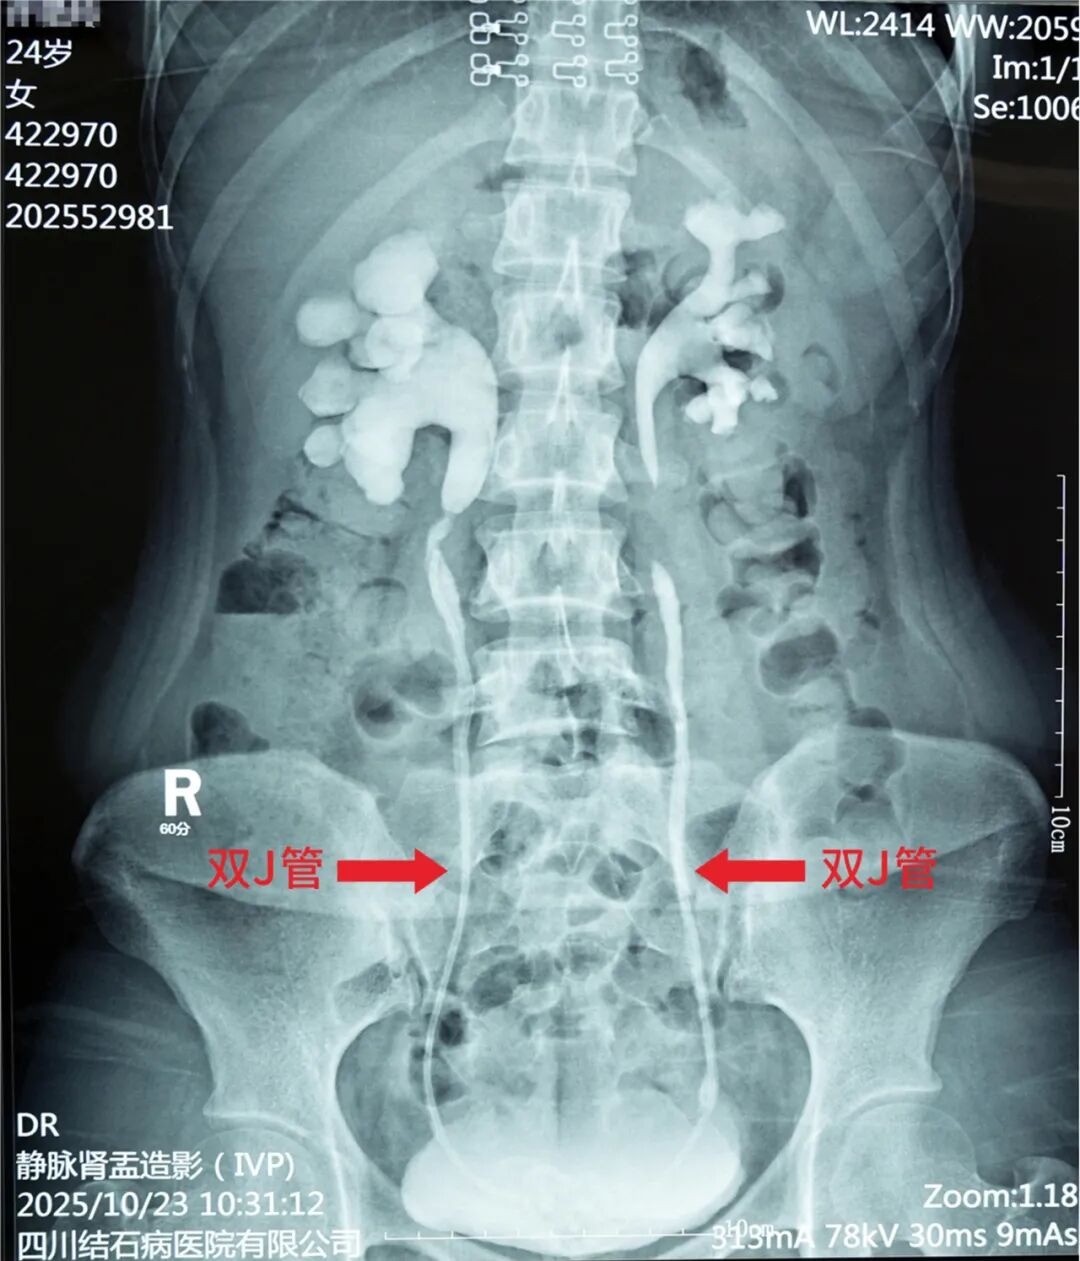

入院后经详细检查,许女士被诊断为右肾结石、右侧输尿管结石、膀胱结石及双肾积水,双肾功能轻-中度受损。而这一切的“罪魁祸首”,竟是她两年多前怀孕时为缓解肾积水,在双侧输尿管内置入、随后却被遗忘的两根双J管。

面对许女士的病情,常立高教授先行实施“膀胱镜下碎石取石术”,顺利将膀胱内一颗直径约3×2.5厘米的结石击碎取出,并同步将左侧输尿管内的双J管轻松取出。然而,右侧输尿管中的双J管被结石紧密包裹,取出难度显著增加。